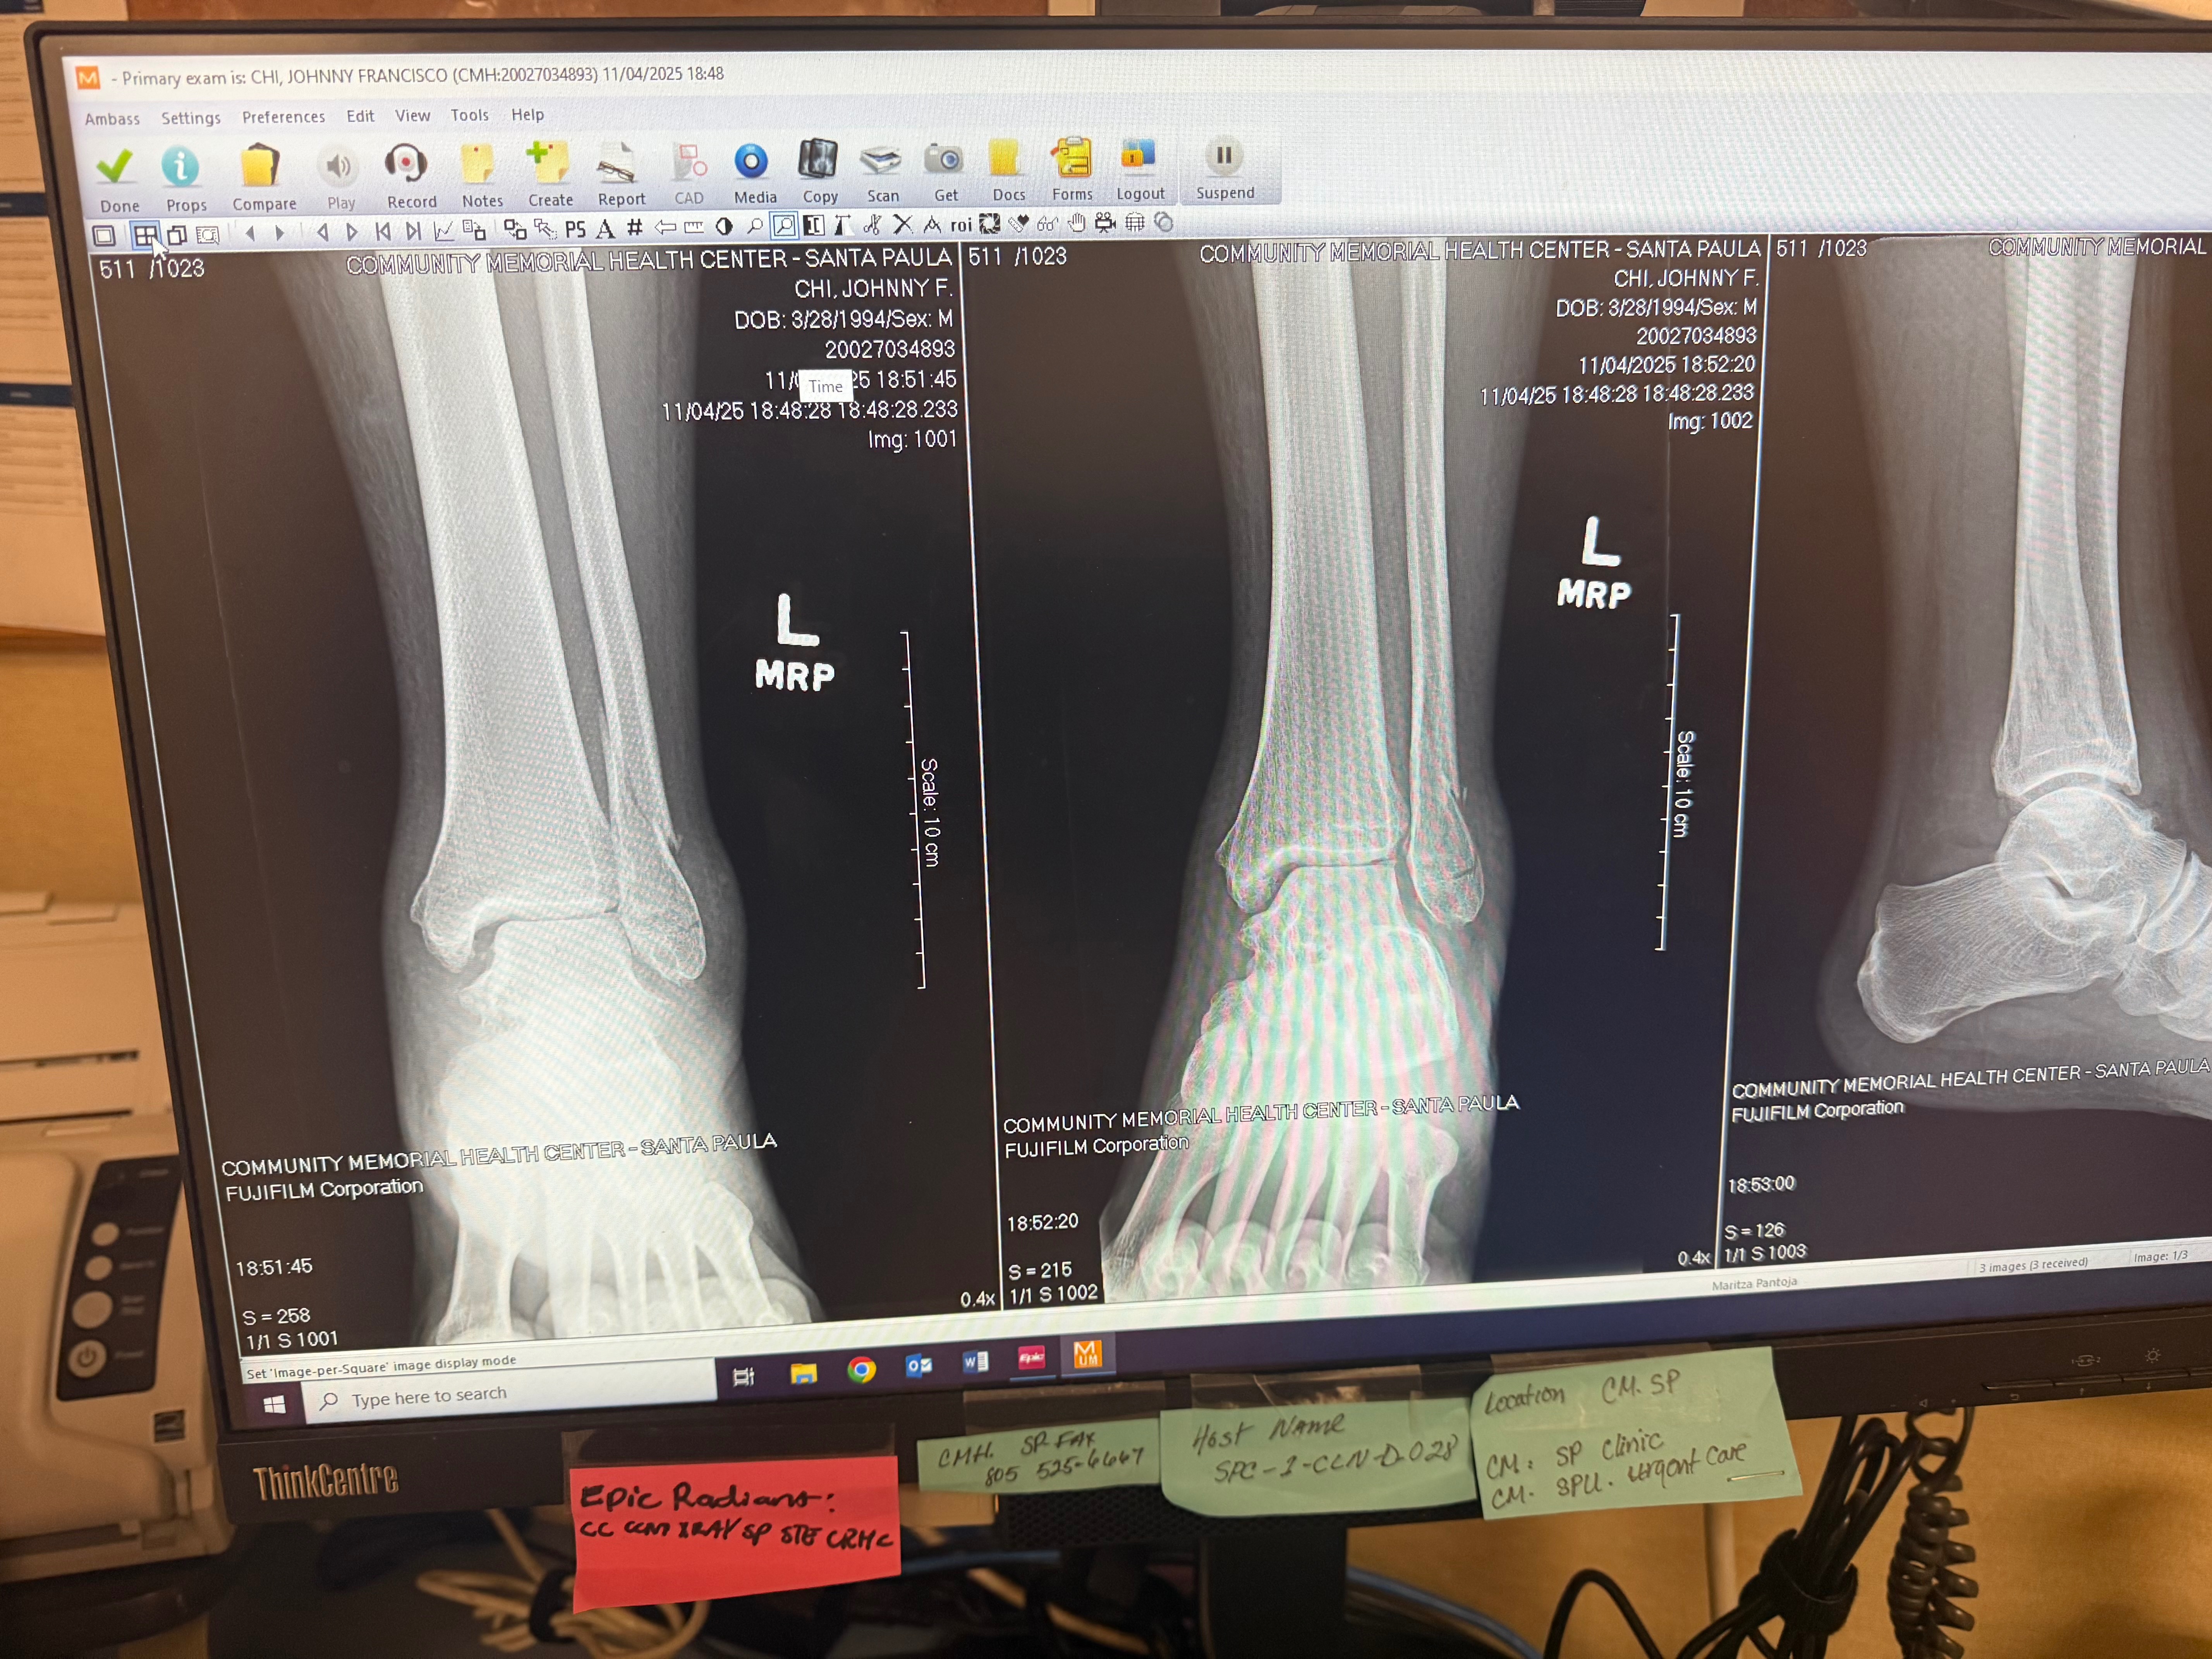

We’re reaching out on behalf of our Azar’s Sports Bar & Grill family to support one of our incredible team members, Johnny, who recently suffered a serious foot injury.

This injury has unfortunately taken him out of work for the time being, and with medical expenses and household bills adding up, we want to do everything we can to help ease the burden on him and his family while he focuses on healing.